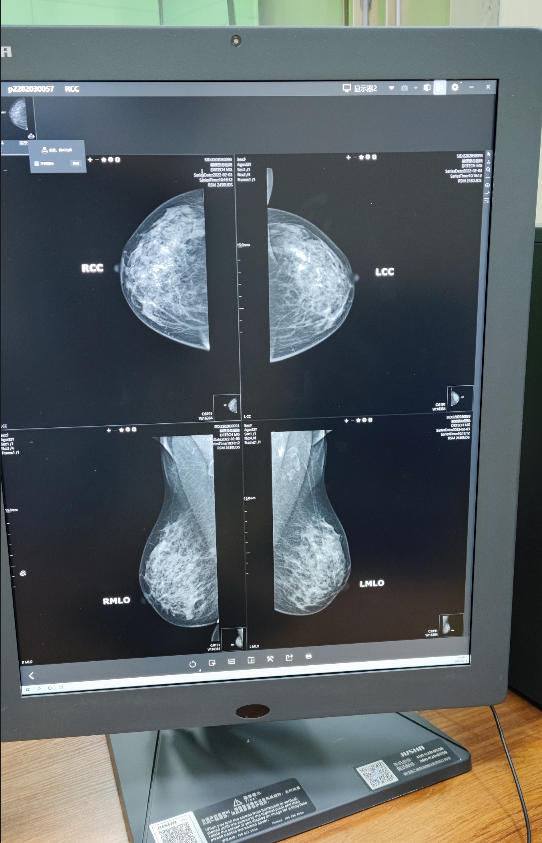

肇源县总医院引进世界先进的全数字化乳腺钨靶机--钨靶非晶硒数字化平板探测乳腺机(简称“钨靶机”)。钨靶机辐射剂量明显减少,可有效地早期发现小于5mm的癌肿,尤其对病人或医生未扪及包块的微小乳癌或微小恶性钙化的检出,是目前最有效的手段。

我院已投入使用的乳腺X线钨靶机是目前世界上最高端的全数字化乳腺X线机,该设备具有更清晰的图像,能够让医生更早发现乳腺病变;设备别具一格的创新技术和设计非常适合女性致密型乳腺,穿透力更强,辐射率更低等优点。乳腺诊断工作站带有功能全面的图像处理软件,可基于不同组织的特征性曲线分别增强处理,实现在同一幅图像上,皮肤、腺体、脂肪等乳房组织及钙化、肿块等病变均能有优异的对比度显示,协助医生方便、有效的工作。该设备可以在短暂的扫描过程中,在不同角度获得乳房的影像,然后将这些独立的影像重建成一系列高分辨率的断层影像,单独显示或以连续播放的形式动态显示。

新一代数字非晶硒大平板式乳腺摄影检查使图像更清晰,早期乳腺癌的诊断率更高,其鉴别良、恶性肿瘤的准确率甚至可达90%以上。这台全新高端乳腺X线机的落户,大大提高了早期乳腺癌检出率,是每一位就诊患者的福音。

3、常规检查需要拍摄四张照片,是双侧轴位及双侧侧斜位;